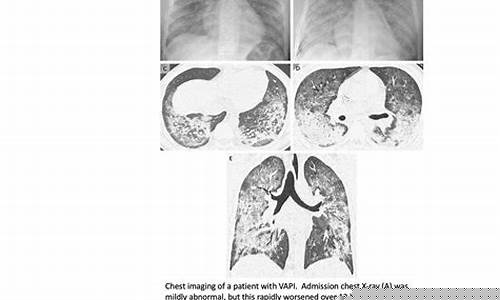

美电子烟肺炎(Vaping-associated lung injury,简称VALI)是指由于吸入电子烟所含的有害物质,导致肺部发生急性损伤的一种疾病。它通常表现为急性呼吸困难、胸痛、咳嗽等症状,严重时可能导致呼吸衰竭,甚至危及生命。